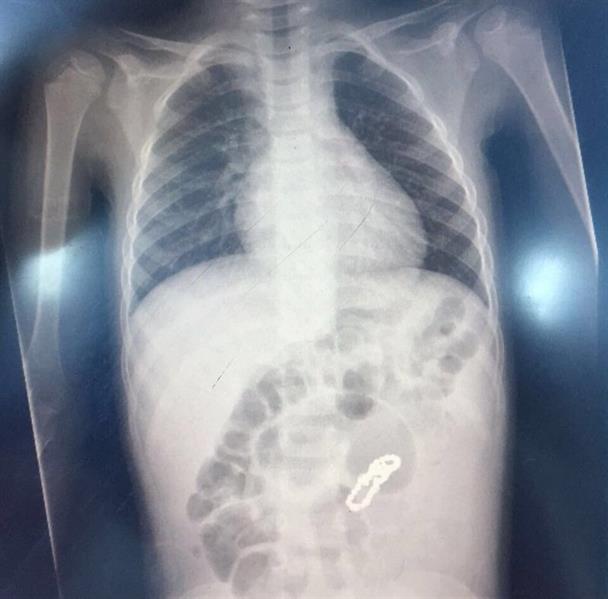

وأتضح من خلال الأشعة التي أجريت له في أحد المستشفيات الخاصة سابقاً وجود جسم غريب يشبه القطع المعدنية الشبكية في البطن.

وعلى الفور تم إجراء عملية جراحية استكشافية إثر حالته، واكتشف الفريق الطبي وجود ثقوب في الأمعاء الدقيقة وناصور بين أجزاء الأمعاء المتلاصقة نتيجة بلع القطع المغناطيسية، مما أدى إلى ثقوب في الأمعاء وأجري للطفل قص الأجزاء المثقوبة وتوصيلها ويتمتع الطفل حالياً بحالة صحية مستقرة.